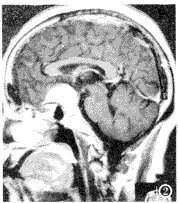

14例蝶鞍外肿瘤中,矢状面及冠状面显示4例视交叉受压上抬及7例视交叉受压向下移位,矢状面显示2例视交叉受压向前上方移位及1例视交叉受压向右前移位(图2)。

图2 鞍结节脑膜瘤,视交叉受压后移。